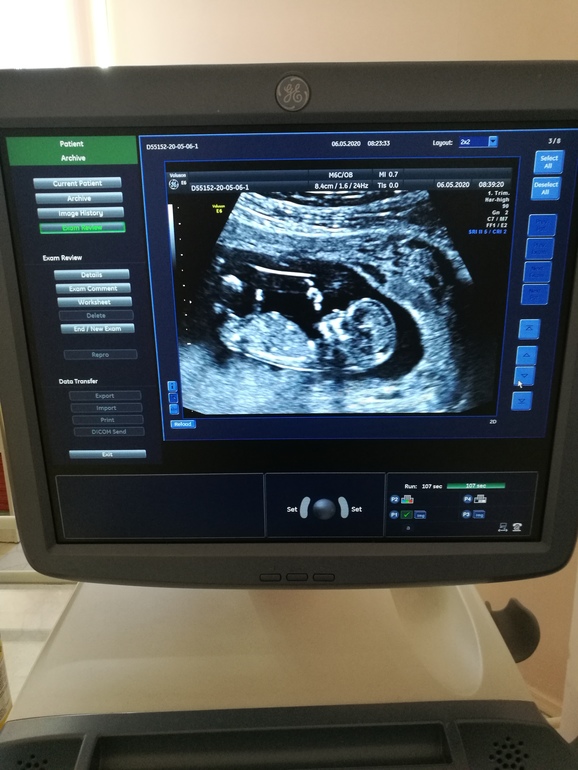

Сходила сегодня на узи, с бусинкой все хорошо, 40минут врач всеми способами пыталась перевернуть ребенка чтобы сделать замеры и фото. Ели получилось.